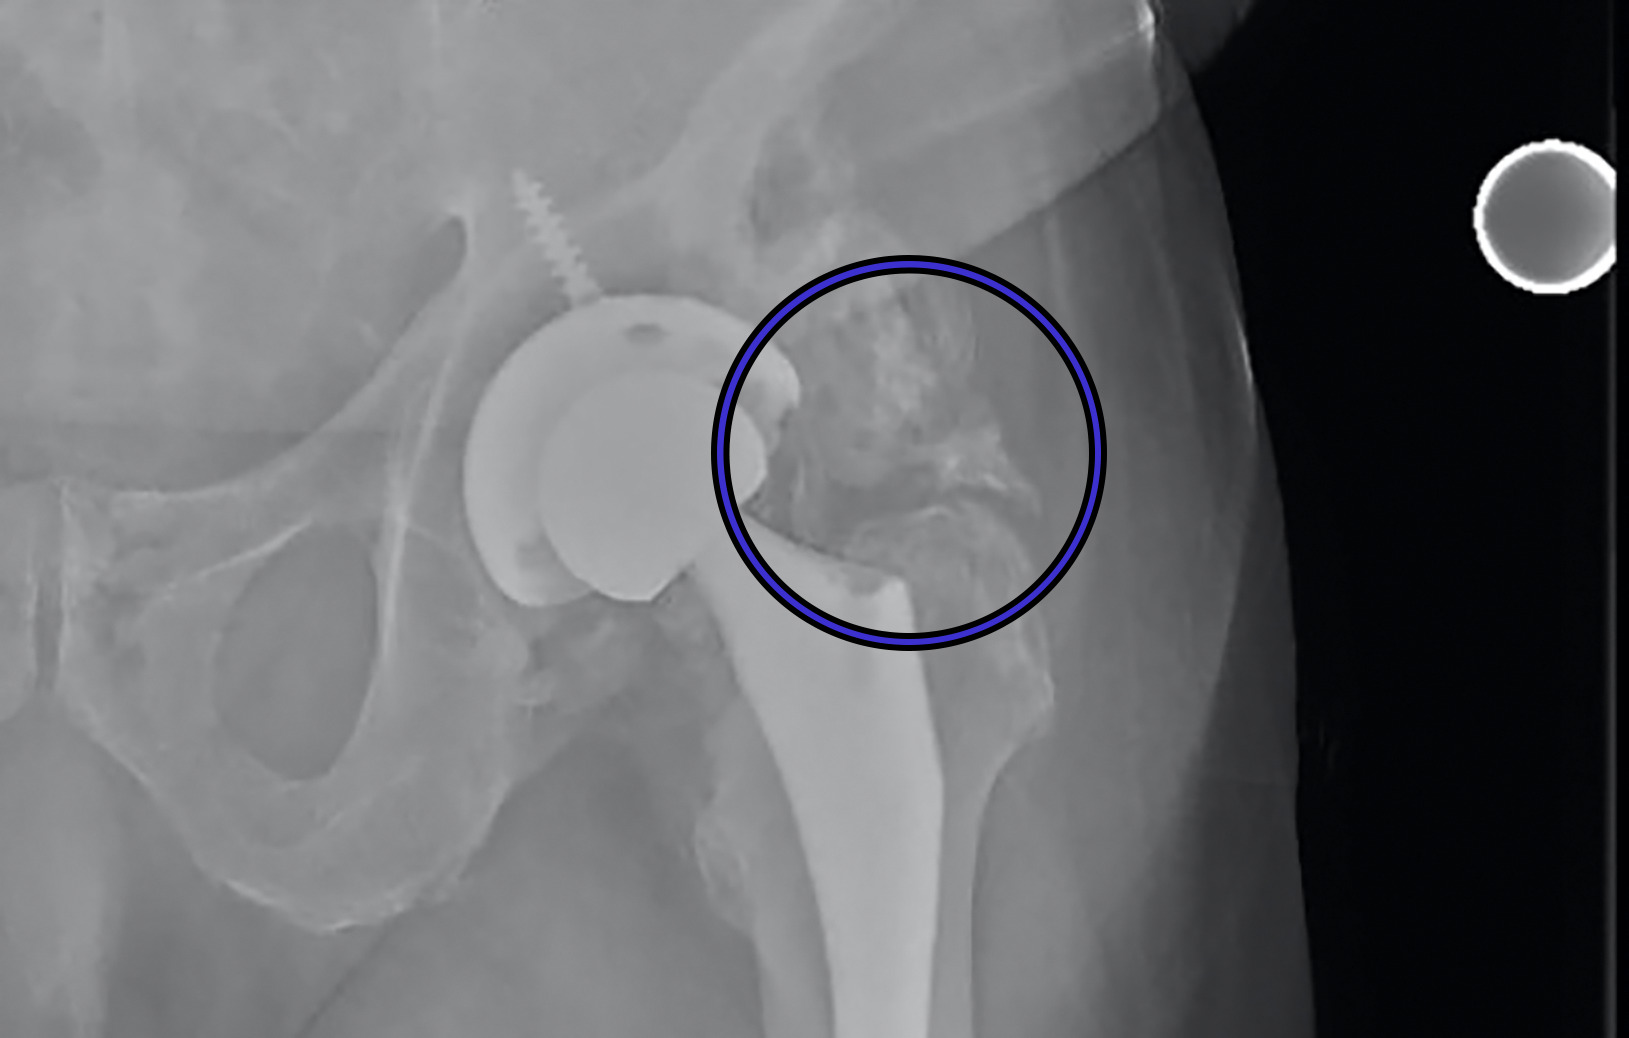

A manual medical record review was conducted by three upper level residents (PK, RD, SY) to investigate if administration of a NSAID was administered during the hospital stay; specifically, both drug type and dose were recorded. DVT prophylaxis, specifically the dose of ASA, was also recorded. Finally, HO was conducted by one senior resident (first author PK), using the Brooker Classification System.18 (Figures 1a-1c) Observing this system, Class 1 is described as islands of bone within the soft tissues about the hip. Class 2 includes bone spurs originating from the pelvis or proximal end of the femur, leaving at least 1 cm. between opposing bone surfaces. Class 3 consists of bone spurs originating from the pelvis or proximal end of the femur, reducing the space between opposing bone surfaces to less than 1 cm. Class 4 shows apparent bone ankylosis of the hip.19 Finally, if post-operative complications such as dislocation occurred this was included in our review of the EMR.